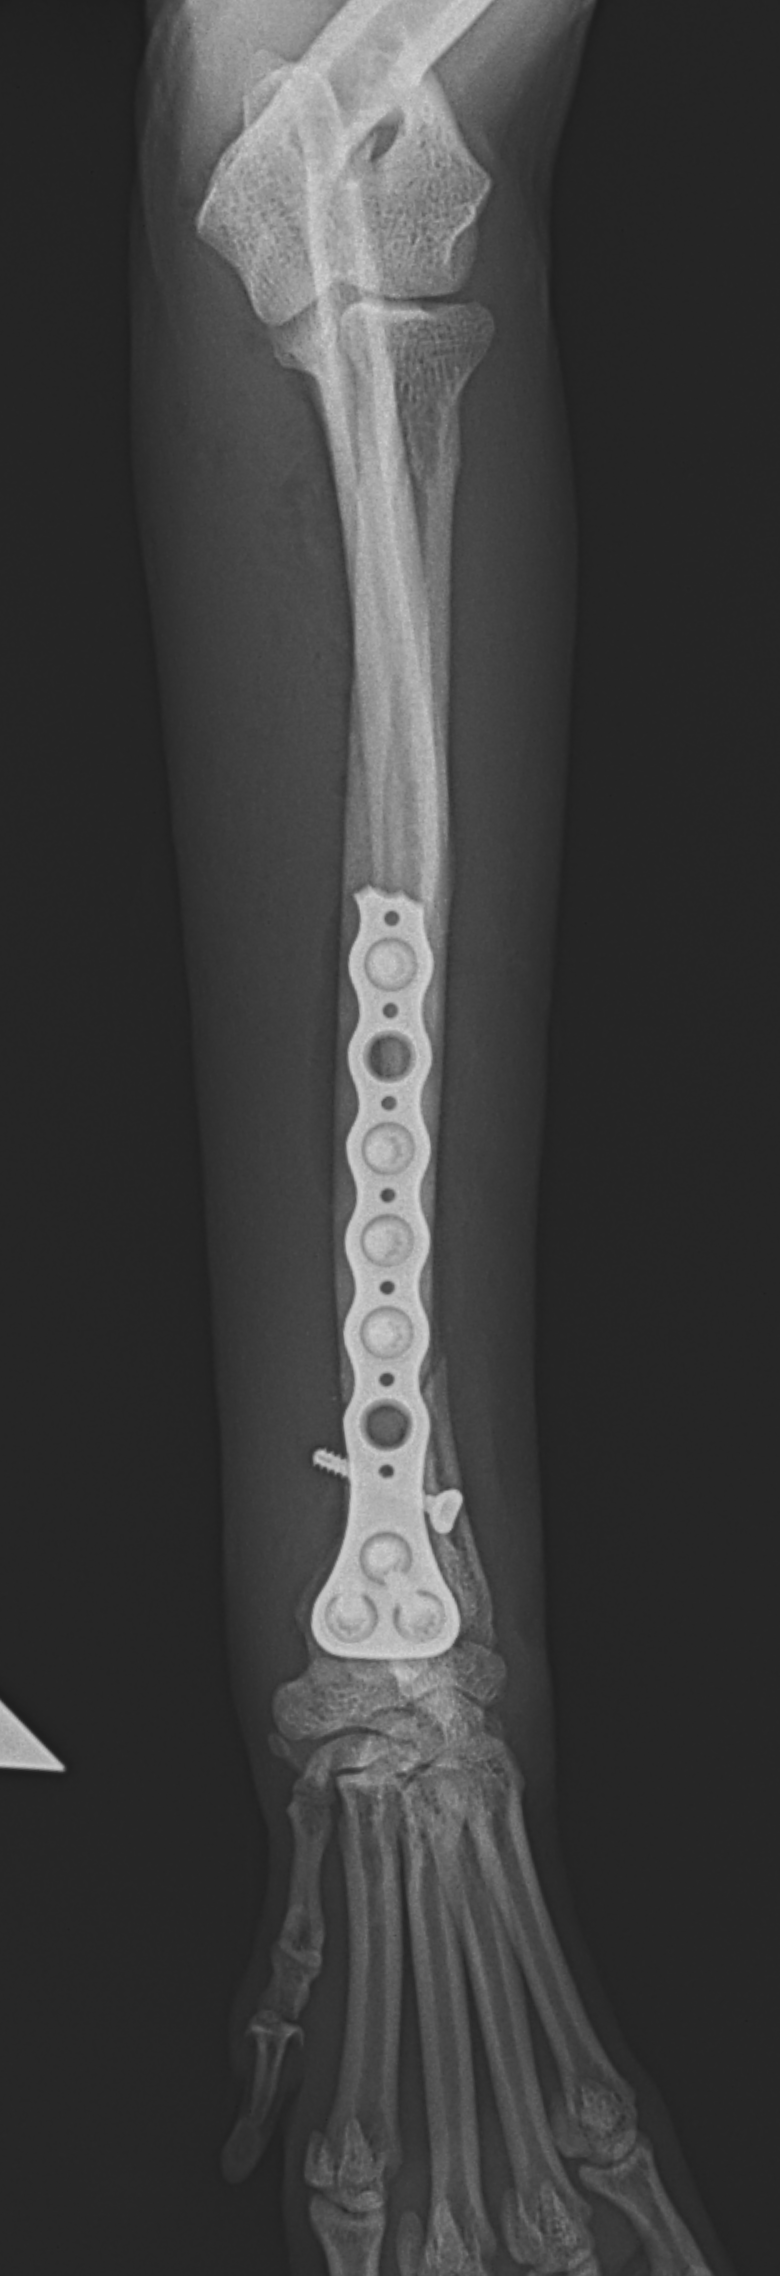

橈骨固定術 #266 6歳のワンコが落下事故により橈骨骨折をしたとの事。関節近傍から斜骨折をしています。1.5のPosition Screw、2.0 TH Plateで固定術を行いました。しばらくは安静が必要です。 症例カテゴリー 放射線治療整形外科軟部組織外科脳神経外科内科腫瘍外科救急・集中治療リハビリテーション科腫瘍内科内視鏡科脳神経科呼吸器外科中医・漢方猫の腎移植循環器科